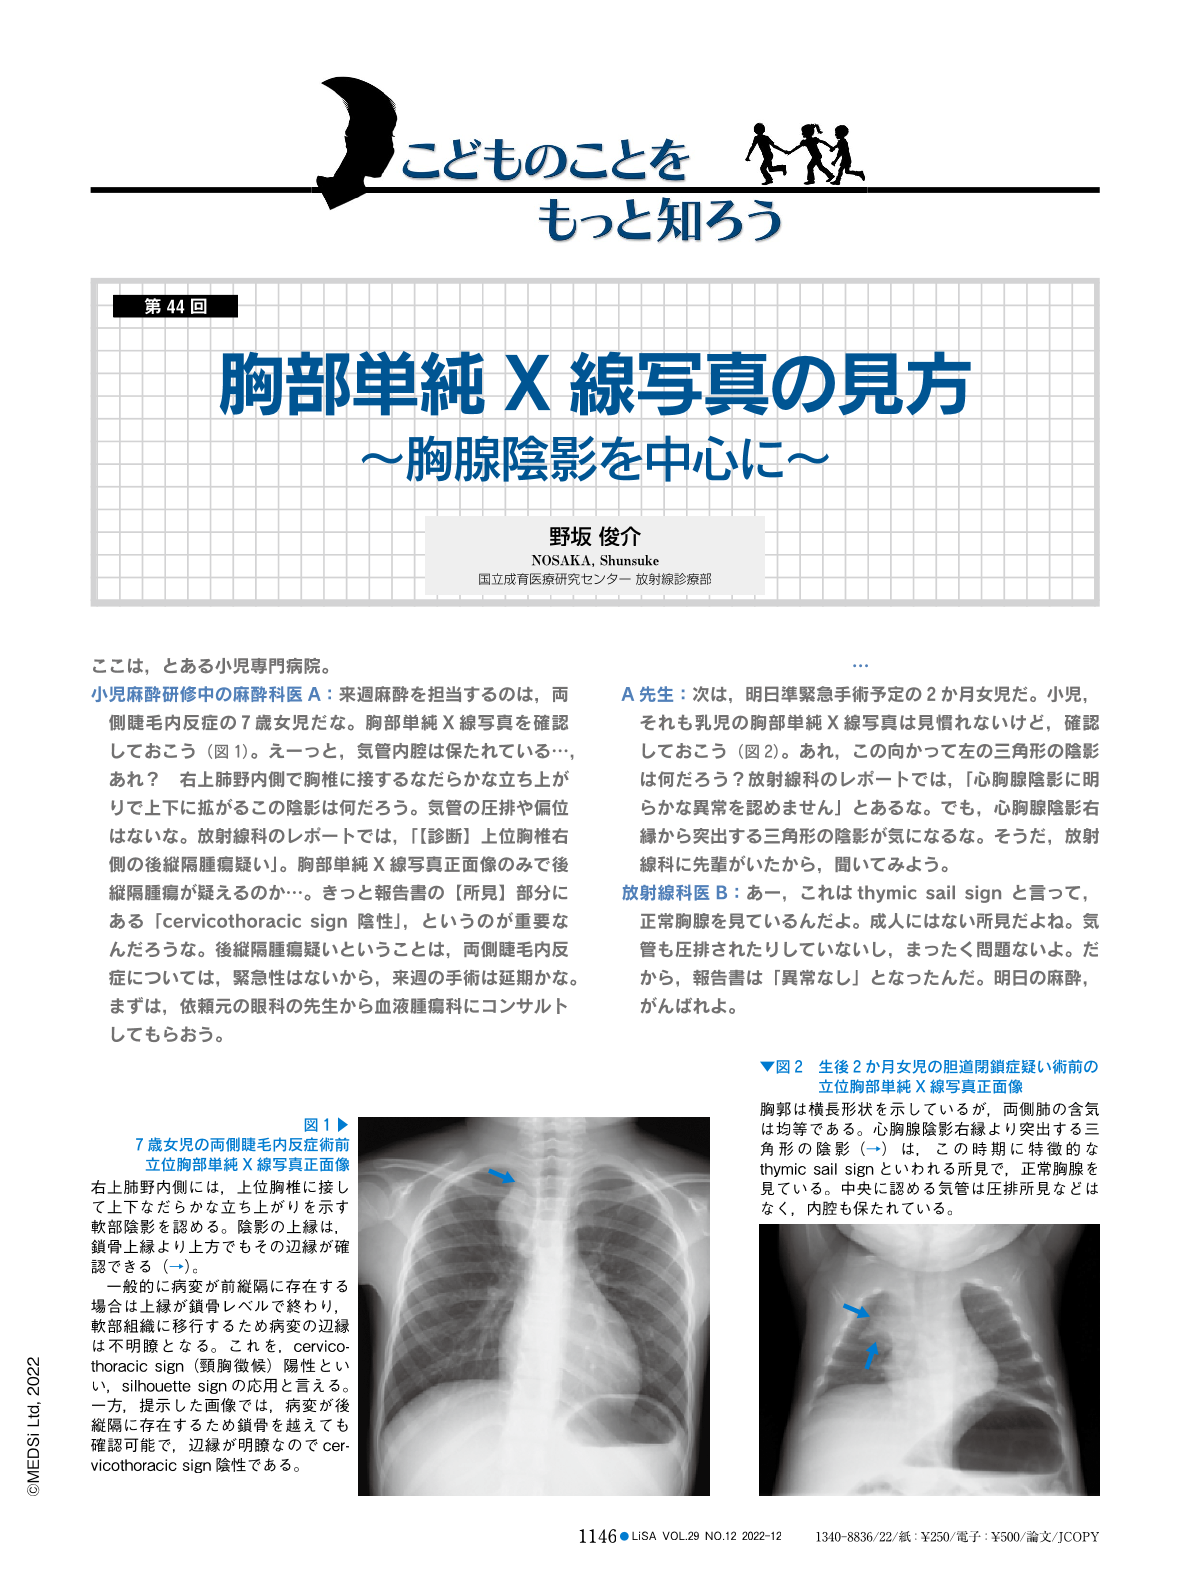

胸部単純X線写真の見方—胸腺陰影を中心に (LiSA 29巻12号) | 医書.jp

胸部単純X線写真の見方—胸腺陰影を中心に (LiSA 29巻12号) | 医書.jp

胸部単純X線写真の見方—胸腺陰影を中心に (LiSA 29巻12号) | 医書.jp,